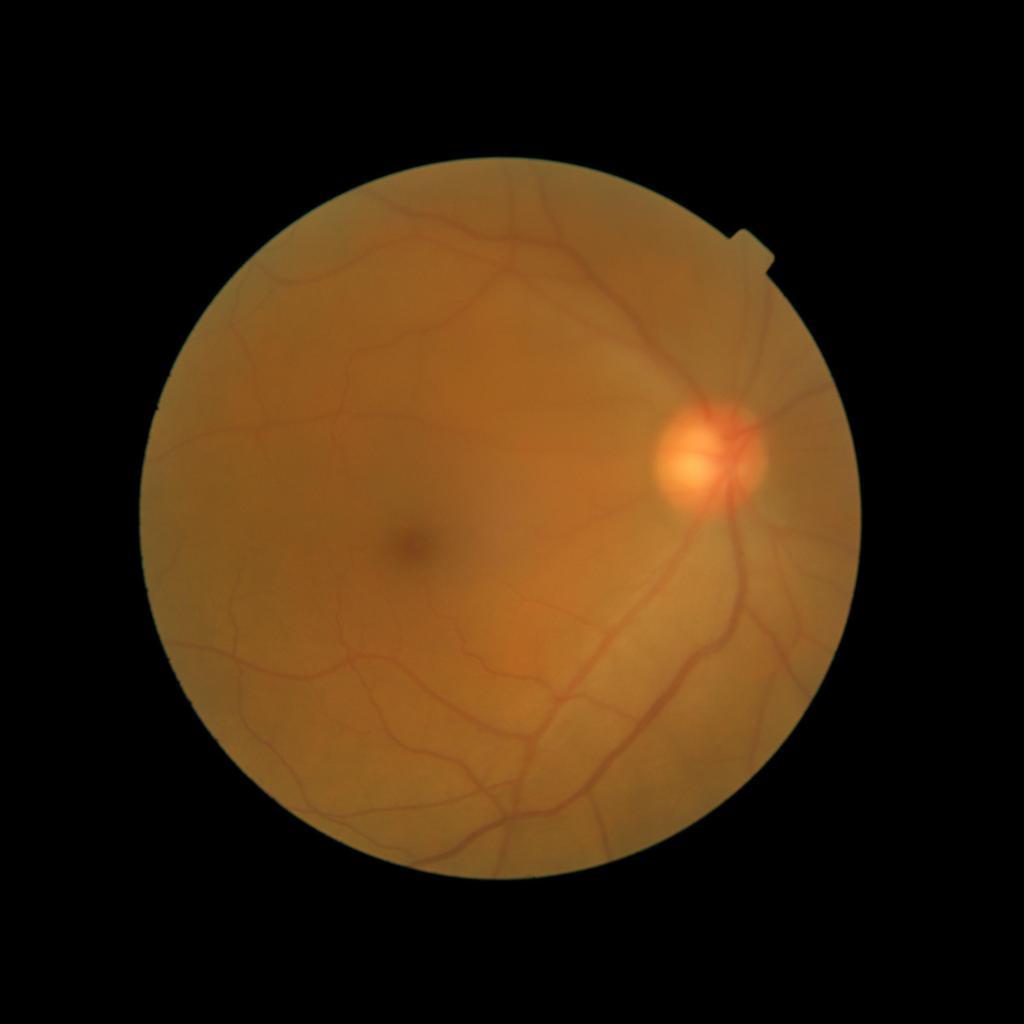

Diffusion models have recently gained significant traction due to their ability to generate high-fidelity and diverse images and videos conditioned on text prompts. In medicine, this application promises to address the critical challenge of data scarcity, a consequence of barriers in data sharing, stringent patient privacy regulations, and disparities in patient population and demographics. By generating realistic and varying medical 2D and 3D images, these models offer a rich, privacy-respecting resource for algorithmic training and research. To this end, we introduce MediSyn, a pair of instruction-tuned text-guided latent diffusion models with the ability to generate high-fidelity and diverse medical 2D and 3D images across specialties and modalities. Through established metrics, we show significant improvement in broad medical image and video synthesis guided by text prompts.

In this work, we focus on the ability of LDMs to generate novel datasets to overcome class imbalances traditionally associated with medical data, and potentially reduce the need for manual annotation of medical 2D and 3D data. We present MediSyn, a pair of text-guided latent diffusion models for broad medical 2D and 3D modality synthesis. To overcome the scarcity of labelled medical data, we leverage a vast corpus of more than 5 million image-caption pairs and 100,000 video-caption pairs collected from the public domain across numerous medical specialties, and integrate comprehensive natural language annotations to develop a pair of versatile diffusion models for the medical domain.

We assembled a set of 5,785,333 medical image-caption pairs, covering 8 specialties and 9 imaging modalities, to train Medisyn’s 2D model. We reserved an additional 1000 image-caption pairs (125 pairs from each specialty) for model evaluation.

Our findings demonstrate Medisyn’s remarkable ability to generate high-fidelity and diverse medical images, image sequences and volumetric scans across various medical subspecialties and imaging modalities. Other medical text-driven diffusion models, such as TauPETGen [42] for tau PET images and GenerateCT [43] for chest CT volumes, have proven successful in generating high-quality images that accurately depict anatomical features and clinical conditions. However, these models are constrained to a single imaging modality and anatomical region, thereby restricting their applicability. Moreover, they were trained on relatively small datasets sourced from a limited number of institutions, which could lead to more biased outputs. In contrast, Medisyn, having been trained on one of the largest publicly accessible medical image and video datasets to date, is equipped to synthesize data that cover numerous medical disciplines, population groups, and disease states. Leveraging our two models, we can synthesize new medical datasets as well as augment existing ones, potentially improving a wide array of medical machine learning tools, both general and specialized. Additionally, our models can minimize the need to repeatedly fine-tune on specific datasets for generating different imaging modalities, thus reducing computational costs for academic labs.

In summary, we introduced a pair of text-conditional LDMs trained on an extensive medical image and video dataset covering various medical subspecialties and imaging modalities. By generating high-fidelity and diverse medical 2D and 3D images, Medisyn illustrates the potential for a singular framework to broadly address the challenge of data scarcity in healthcare.